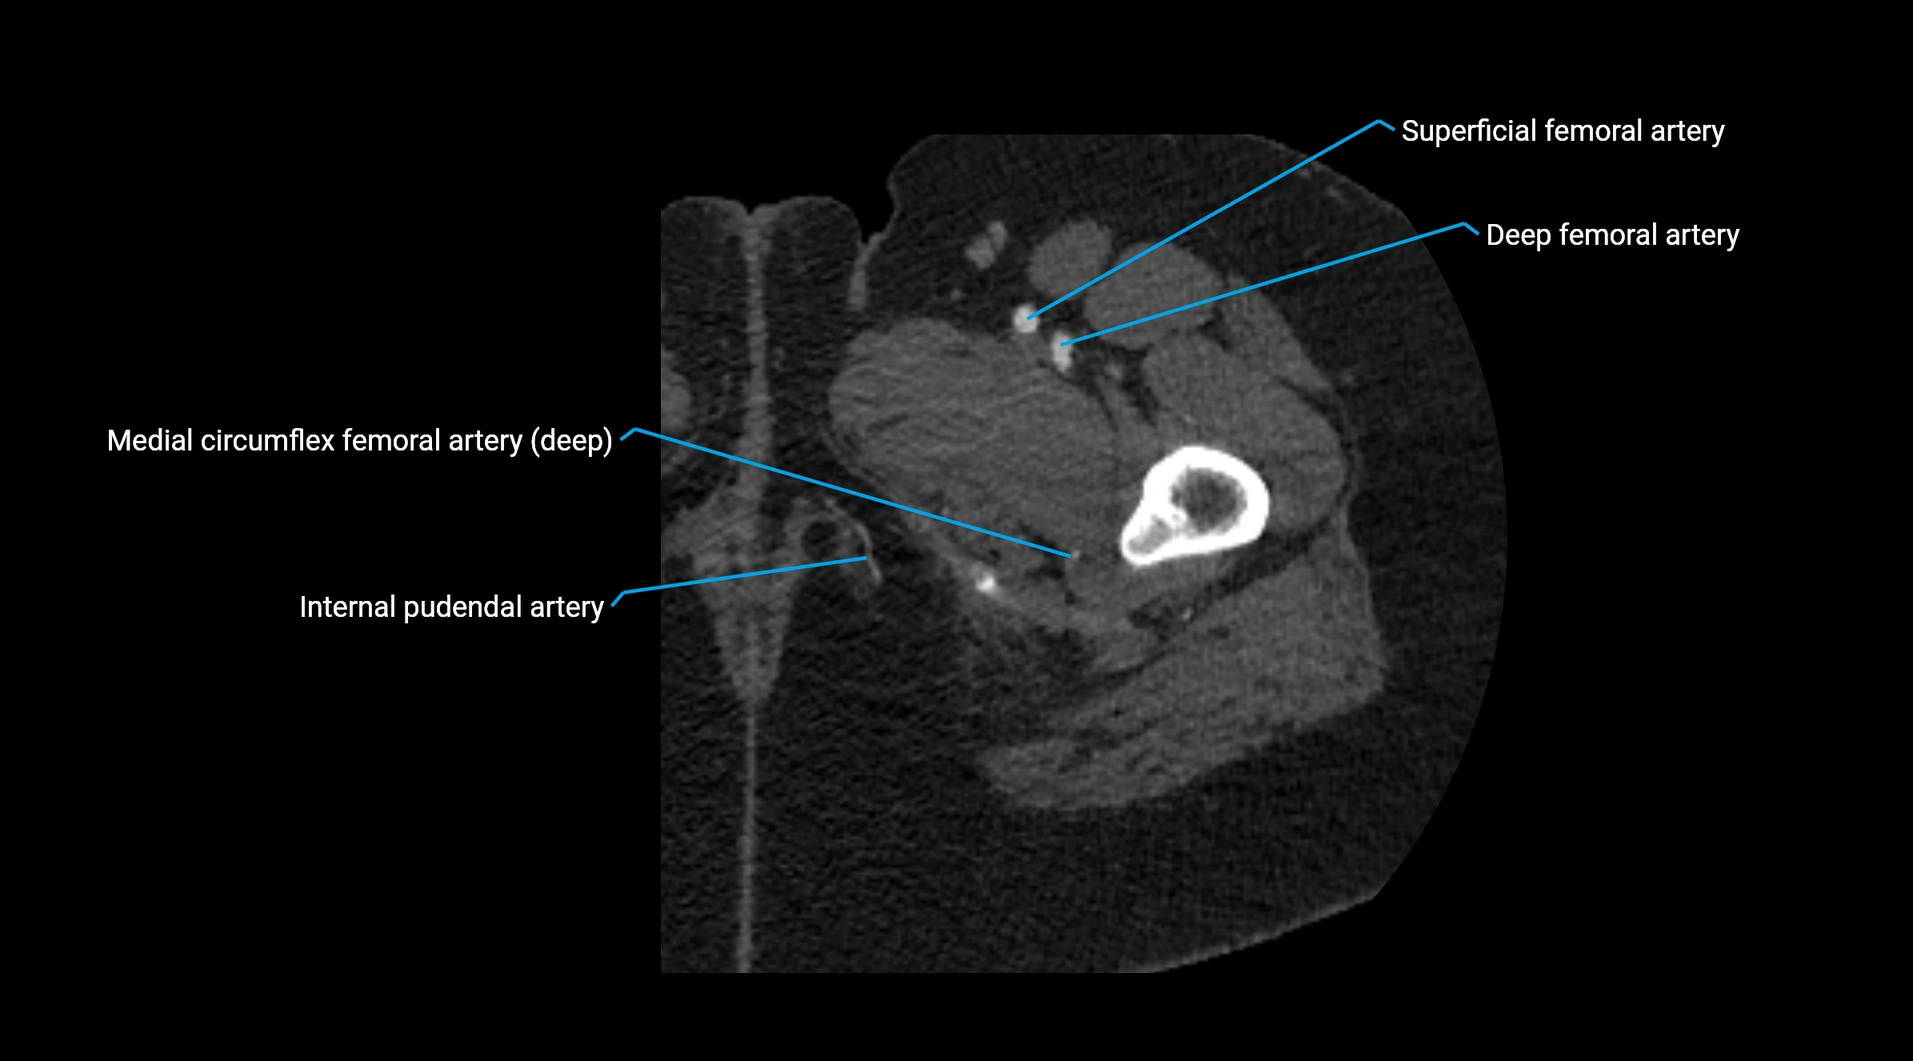

Contrast-enhanced CT (CTA):

• Gold standard for abdominal aortic imaging

• Provides excellent detail of lumen, wall, aneurysm, thrombus, and branch vessels

• Multiplanar and 3D reconstructions help in aneurysm measurement, stent graft planning, and dissection evaluation

• Detects acute rupture, traumatic injury, or occlusion with high sensitivity